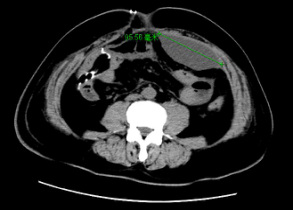

入院后完善相关辅助检查,经引流管造影评估后更换双套管引流右侧腹腔,腹部CT可见腹腔内大量积液,经CT定位后局麻切开引流。

患者经主动冲洗引流右侧腹腔和局麻引流左侧腹腔积液后各项感染指标明显改善。最终用生物蛋白胶将右侧瘘口进行封堵。